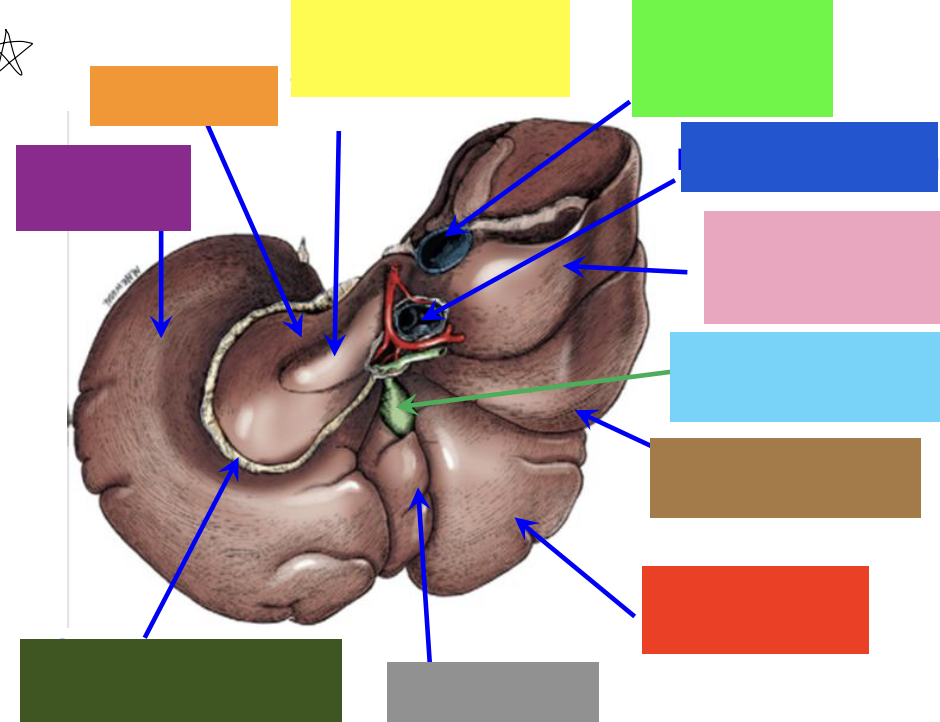

purple box

left lateral lobe

orange box

caudate lobe

yellow box

papillary process of the caudate lobe

neon green box

right lateral lobe

dark blue box

hepatic portal vein

pink box

caudate process of the caudate lobe

light blue box

gall bladder

brown box

right lateral lobe

red box

right medial lobe

grey box

quadrate lobe

dark green box

lesser omentum